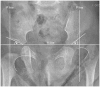

Developmental dysplasia of the hip is a condition characterized by hip joint instability due to acetabular dysplasia in infancy, necessitating precise ultrasound examination. Legg-Calvé-Perthes disease is caused by a temporary disruption in blood flow to the femoral head during childhood, progressing through avascular, fragmentation, re-ossification, and residual stages. Slipped capital femoral epiphysis is a condition where the femoral head shifts medially along the epiphyseal line during adolescence due to stress, such as weight-bearing. Differentiating between transient hip synovitis and septic arthritis may require joint fluid aspiration. Osteomyelitis can be associated with soft tissue edema and osteolysis. When multiple lesions are present, it is essential to distinguish between Langerhans cell histiocytosis and metastatic neuroblastoma. This review will introduce imaging techniques and typical findings for these conditions.